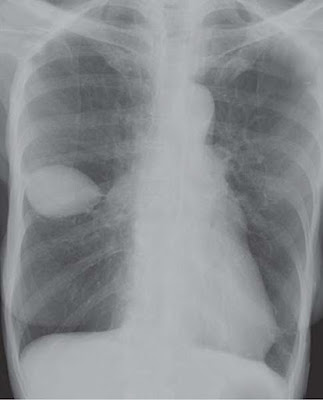

Description: Chest X-ray shows an oval soft tissue density which overlays over most of the minor fissure. It is well-defined, no calcification seen and the surrounding lung is clear.

Diagnosed as Pseudotumor.

Comments And Explanation: Loculation within the fissure gives appearance of a tumor and is referred as pseudotumor. The pulmonary pseudotumor is sharply marginated collection of pleural fluid contained either within an interlobar pulmonary fissure or in a subpleural location adjacent to a fissure. Pseudotumors are identified on chest X-rays on their lenticular pattern.

CT chest confirms a loculated effusion within the fissure with Hounsfield value that of a transudate. The pseudotumor resolves with conservative management.

Most occur in the minor (horizontal) fissure and are seen on both the frontal and lateral radiograph; those that occur in the oblique or major fissure may only be seen on the lateral view. Pseudotumors may be erroneously diagnosed as parenchymal lung nodules or masses.

Clinical Discussion: Pseudotumor or vanishing tumor of the lung is an appropriate designation for a

localized transudative interlobar pleural fluid collection. It derives its name from its frequent resemblance to a tumor on X-ray chest and from its tendency to vanish following appropriate management.

Encapsulation is due to adhesions between contiguous pleural surfaces. Therefore, it is often seen after episodes of pleuritis. The pleural encapsulation can be mistaken for pulmonary consolidation, collapse, or a mediastinal tumor. The borders of a loculated effusion are convex unlike pulmonary collapse or consolidation. There may be pleural thickening elsewhere in the thorax. It is most commonly seen in the minor fissure.

The possibility of a vanishing lung tumor should be considered and excluded in any patient presenting with congestive heart failure or apparent lung mass on a chest X-ray.